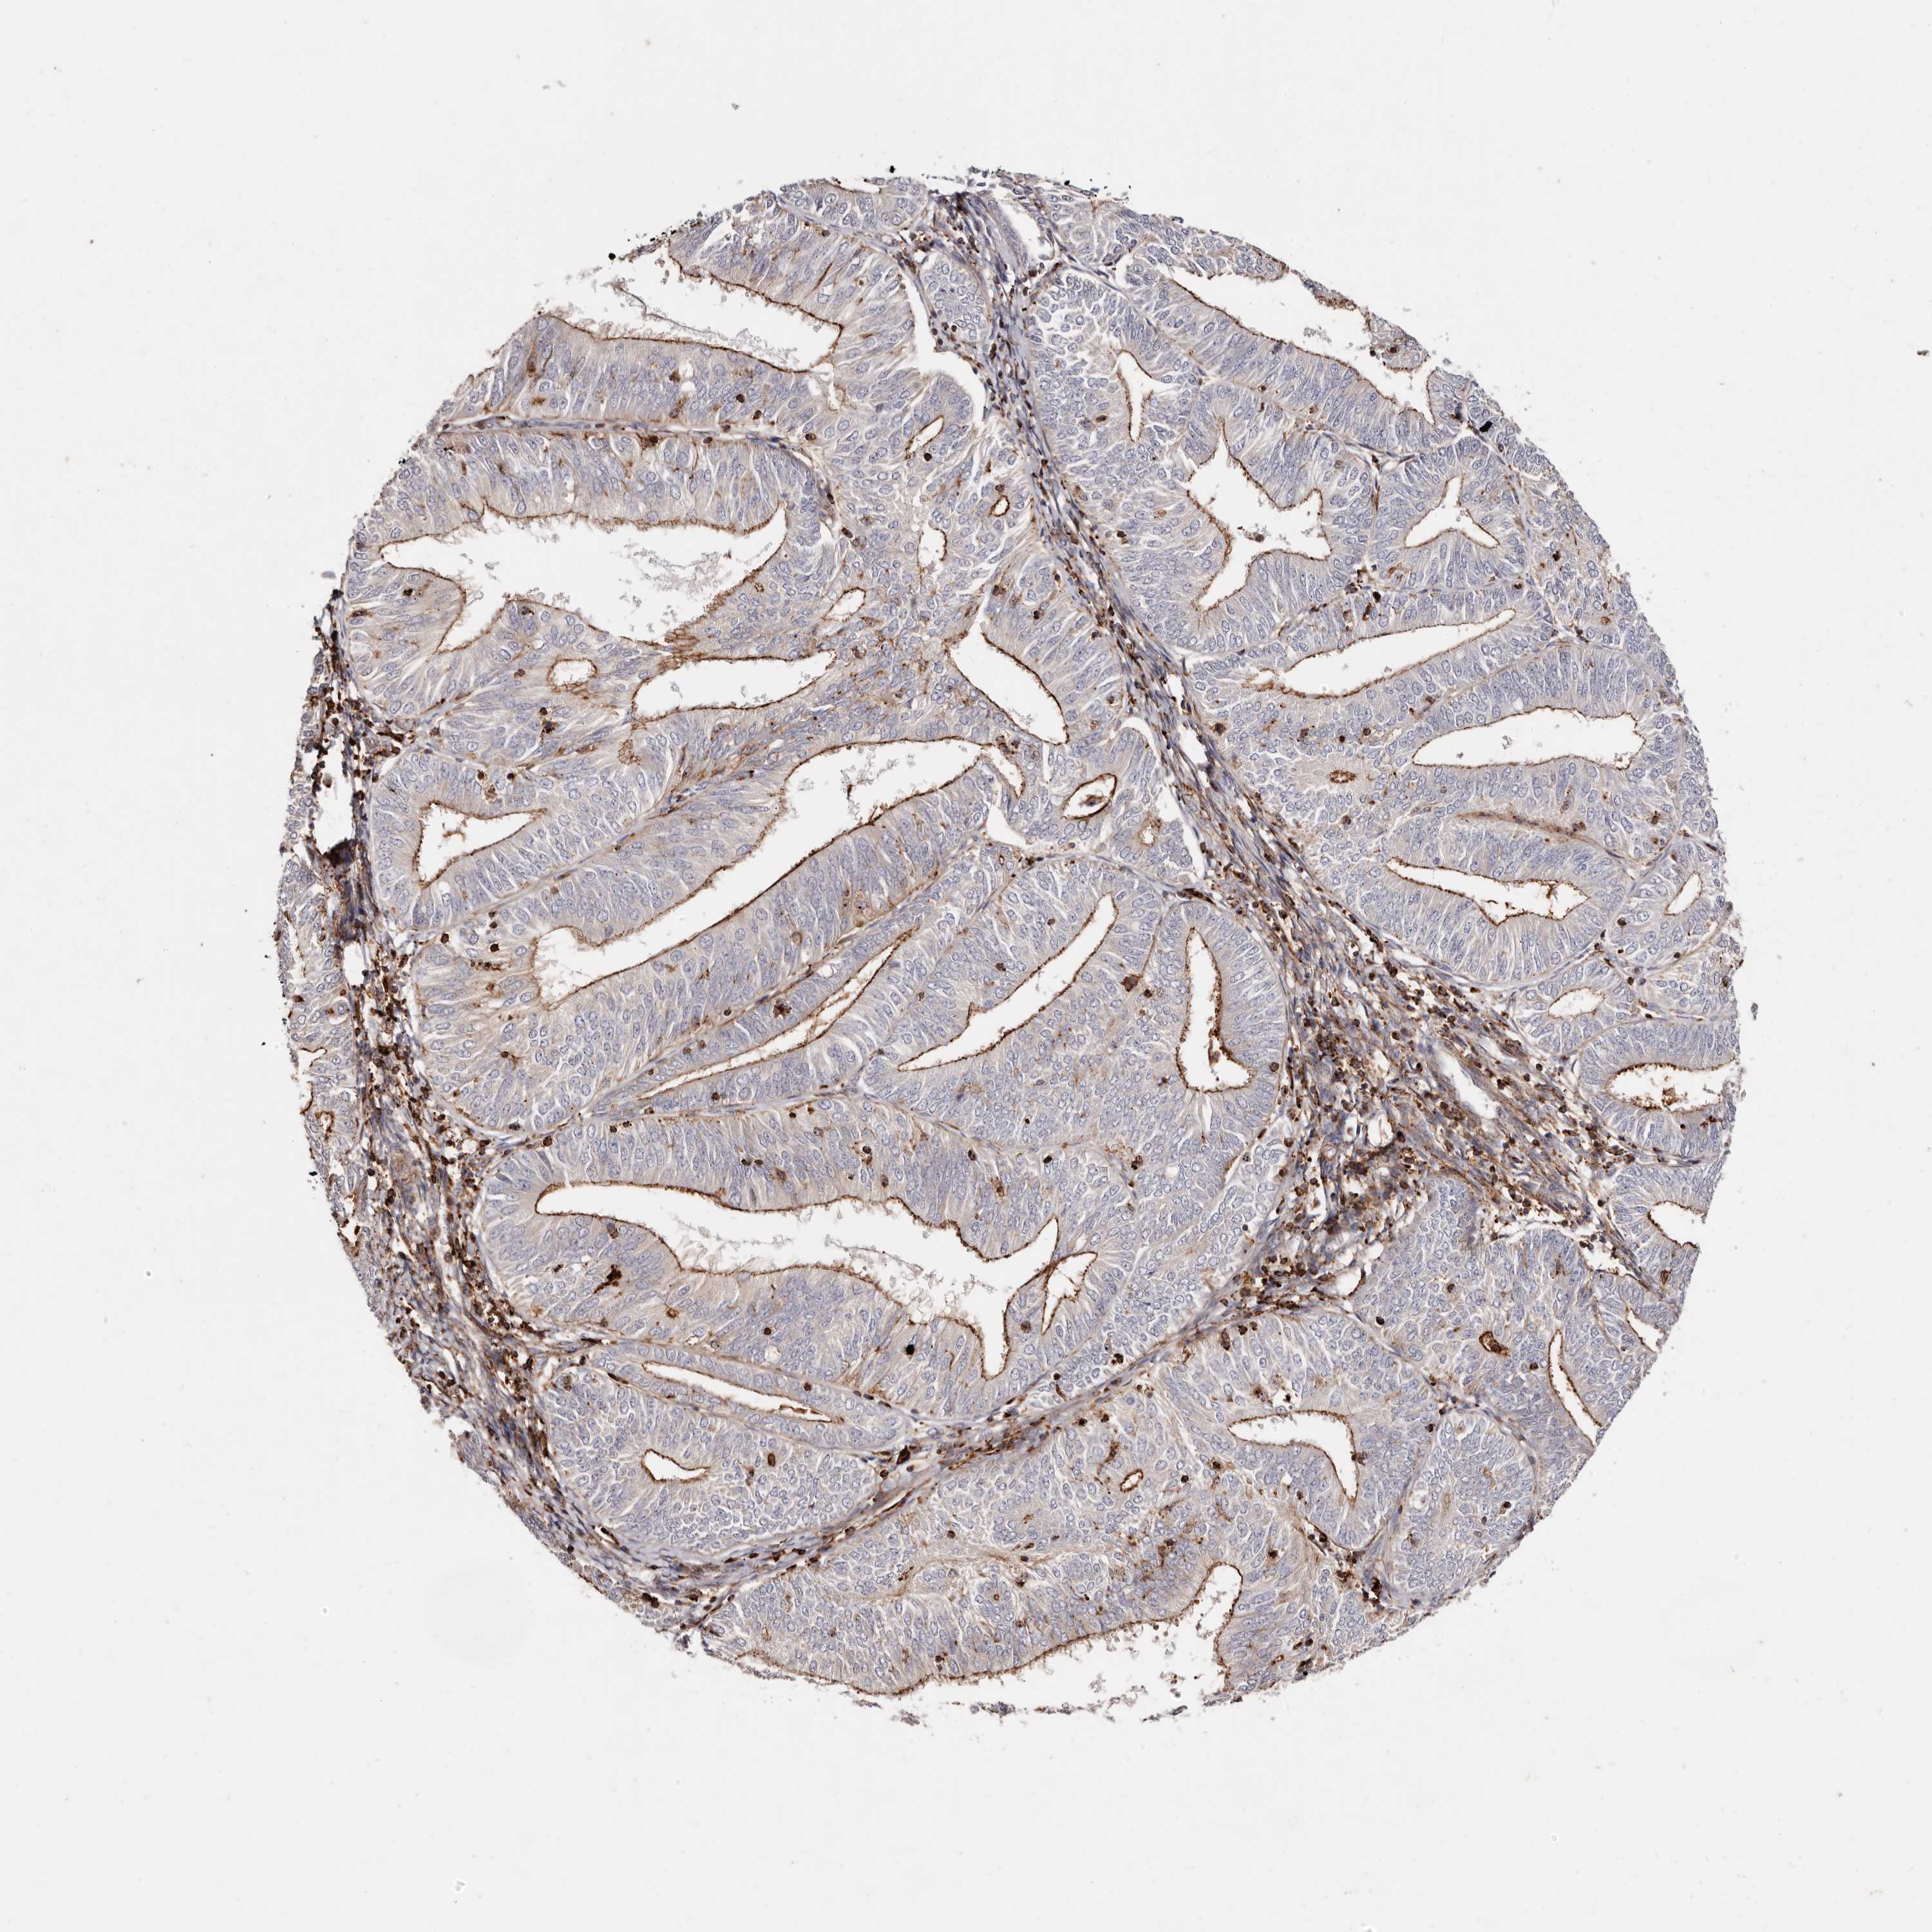

ENDOMETRIAL CANCER - Protein expressioni

A mouse-over function shows sample information and annotation data. Click on an image to view it in a full screen mode. Samples can be filtered based on level of antibody staining by selecting one or several of the following categories: high, medium, low and not detected. The assay and annotation is described here.

Note that samples used for immunohistochemistry by the Human Protein Atlas do not correspond to samples in the TCGA dataset.

Antibody stainingi

Antibody staining in the annotated cell types in the current human tissue is reported as not detected, low, medium, or high, based on conventional immunohistochemistry profiling in selected tissues. This score is based on the combination of the staining intensity and fraction of stained cells.

Each image is clickable and will lead to virtual microscopy that enables deeper exploration of all samples and also displays staining intensity scores, fraction scores and subcellular localization as well as patient and tissue information for each sample.

Antibody HPA004912

Antibody HPA013350

Antibody CAB012209

Staining

High

Medium

Low

Not detected

Intensity

Strong

Moderate

Weak

Negative

Quantity

>75%

75%-25%

<25%

None

Location

Nuclear

Cytoplasmic/membranous

Cytoplasmic/membranous,nuclear

Adenocarcinoma, NOS

Adenocarcinoma, metastatic, NOS